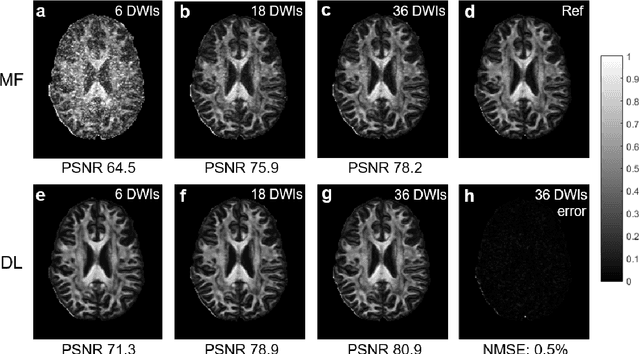

Abstract:Diffusion tensor imaging (DTI) is widely used to examine the human brain white matter structures, including their microarchitecture integrity and spatial fiber tract trajectories, with clinical applications in several neurological disorders and neurosurgical guidance. However, a major factor that prevents DTI from being incorporated in clinical routines is its long scan time due to the acquisition of a large number (typically 30 or more) of diffusion-weighted images (DWIs) required for reliable tensor estimation. Here, a deep learning-based technique is developed to obtain diffusion tensor images with only six DWIs, resulting in a significant reduction in imaging time. The method uses deep convolutional neural networks to learn the highly nonlinear relationship between DWIs and several tensor-derived maps, bypassing the conventional tensor fitting procedure, which is well known to be highly susceptible to noises in DWIs. The performance of the method was evaluated using DWI datasets from the Human Connectome Project and patients with ischemic stroke. Our results demonstrate that the proposed technique is able to generate quantitative maps of good quality fractional anisotropy (FA) and mean diffusivity (MD), as well as the fiber tractography from as few as six DWIs. The proposed method achieves a quantification error of less than 5% in all regions of interest of the brain, which is the rate of in vivo reproducibility of diffusion tensor imaging. Tractography reconstruction is also comparable to the ground truth obtained from 90 DWIs. In addition, we also demonstrate that the neural network trained on healthy volunteers can be directly applied/tested on stroke patients' DWIs data without compromising the lesion detectability. Such a significant reduction in scan time will allow inclusion of DTI into clinical routine for many potential applications.